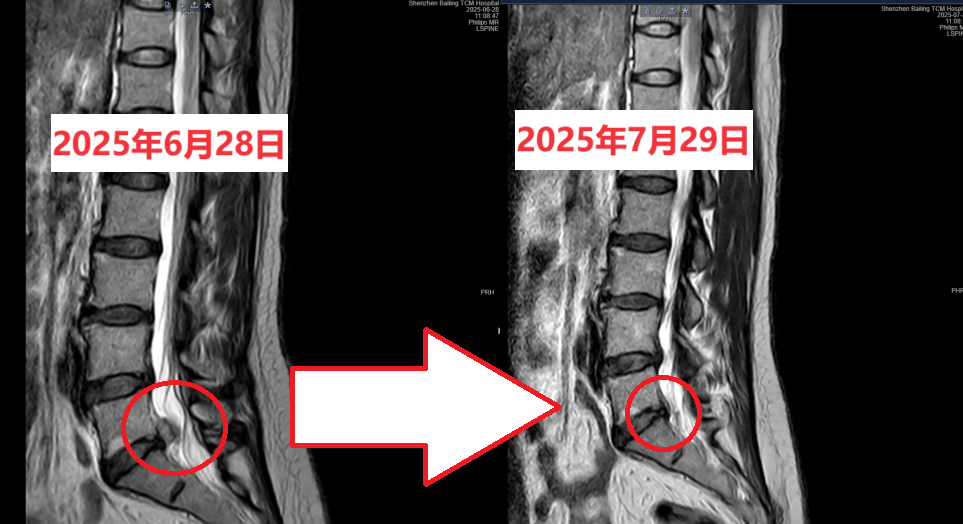

进一步查腰椎MRI(2025年6月28日)提示:腰5/骶1椎间盘右后突出伴神经根炎。当时也有怀疑是神经根肿瘤(神经根水肿水肿太严重了),随着后续的保守治疗,症状逐渐缓解,解除了神经根肿瘤的警报。

1个月后:患者腰痛伴下肢麻痛、乏力明显减轻。腰部无压痛,直腿抬高试验阴性,双下肢肌力、浅感觉基本对称。予复查腰椎MRI(2025年7月29日)提示:对比2025年6月28日MRI片子,腰5/骶1椎间盘突出明显缩小,神经根水肿明显好转。

复查MRI结果,直观展示了椎间盘突出物缩小/回缩 的现象。